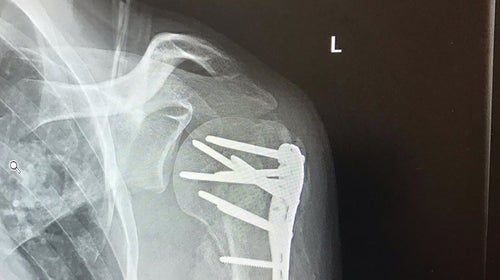

Andrew Bernstein鈥檚 repaired humorous

Full body CAT scans and further examinations revealed catastrophic damage: a lacerated liver, bleeding around his heart, and many, many broken bones, including all of his ribs, his sternum, and his pelvis in three places. There was also damage to his spinal cord.

Bernstein: I've been on my back for at that point, like more than a month. And my legs had gone from like elite level bike racer to just complete atrophy. And my left arm at that time was like very much still recovering from being repaired and I could like barely use it to stabilize myself.